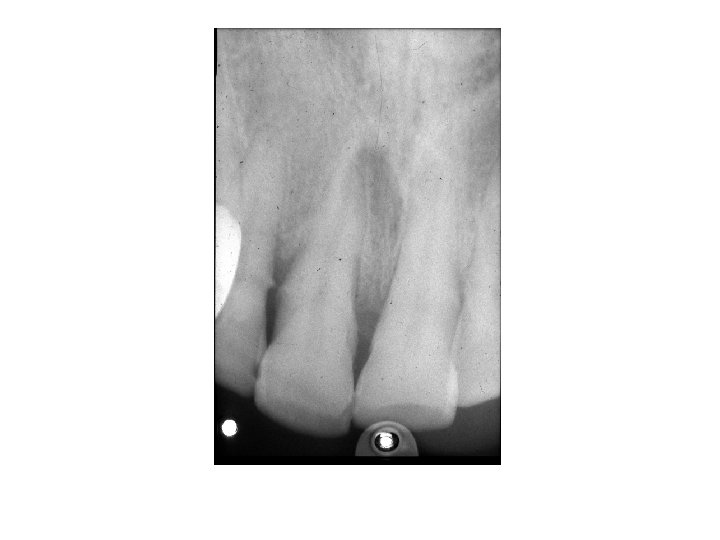

Akute Apikale Parodontitis • PRIMER Symptome: Akute Entzündung in der Umgebung der Wurzelspitze. Dauerschmerz in der Umgebung des Zahnes, Perkussionsschmerz, Der Patient hat das Gefühl, der Zahn sei länger geworden. Ursache: Pulpitis, Trauma, Caries, Röntgen: Im Röntgenbild bietet die primär-akute apikale Parodontitis zunächst keine Veränderungen. Nach einigen Tagen wird der durch die Entzündung ausgelöste Knochenabbau als diffuse Aufhellung in der Umgebung der Wurzelspitze erkennbar. , + Periodontale Spalt ist breiter. • SEKUNDER Symptome: Akute Exazerbation einer primär-apikalen Parodontitis. Röntgen: Ähnlich wie chronische apikale Parodontitis

Chronische Apikale Parodontitis • Symptome: Langsamer Verlauf. Keine Schmerzen, Devitalität des betroffenen Zahnes. • Ursache: Infektion über den Wurzelkanal eines pulpentoten Zahnes • Röntgen: Im Röntgenbild apikale Aufhellung oder Parodontalspaltverbreiterung. +Knochensklerose/ Knochenverdünnung